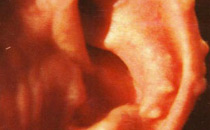

耳廓

例子

病症描述:左耳廓对耳轮局部反复红肿疼痛,左耳廓对耳轮处出现多处花生粒大小肿块,红肿疼痛反反复作,局部无溃破。

在线客服医院电话

(注:如出现以上症状请及时在线导诊或者到院就医。)